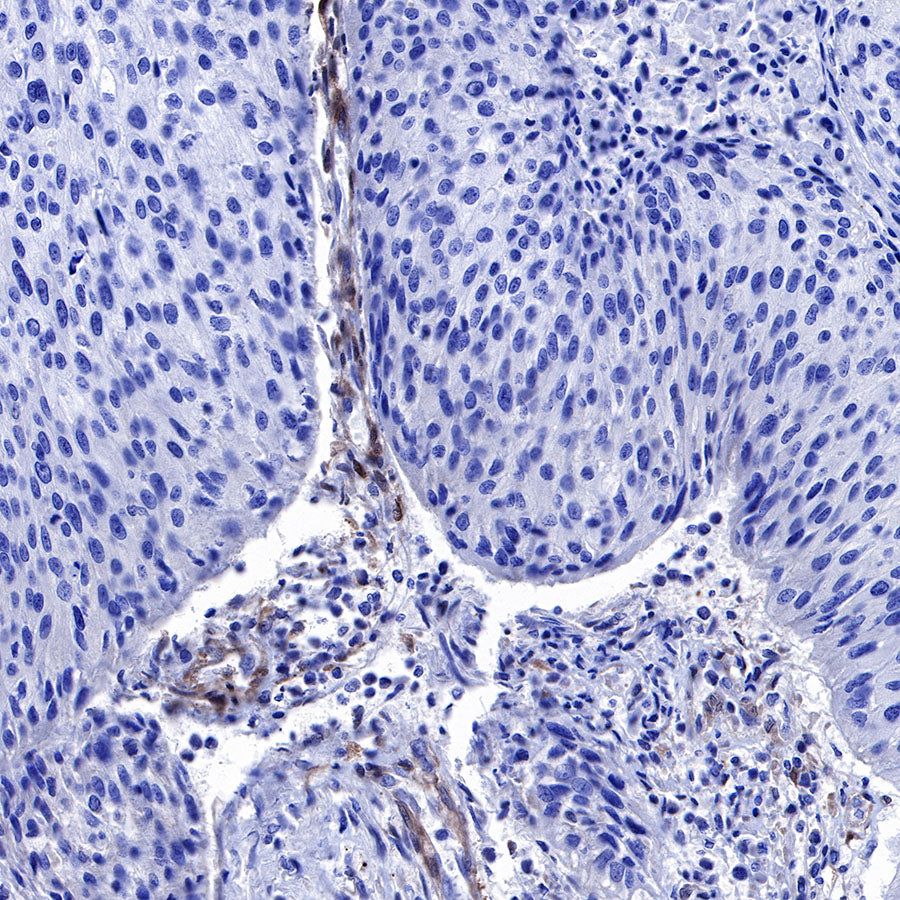

Immunohistochemistry

IHC shows positive staining in paraffin-embedded human cervical carcinoma. Anti-PTEN antibody was used at 1/500 dilution, followed by a HRP Polymer for Mouse & Rabbit IgG (ready to use). Counterstained with hematoxylin. Heat mediated antigen retrieval with Tris/EDTA buffer pH9.0 was performed before commencing with IHC staining protocol.